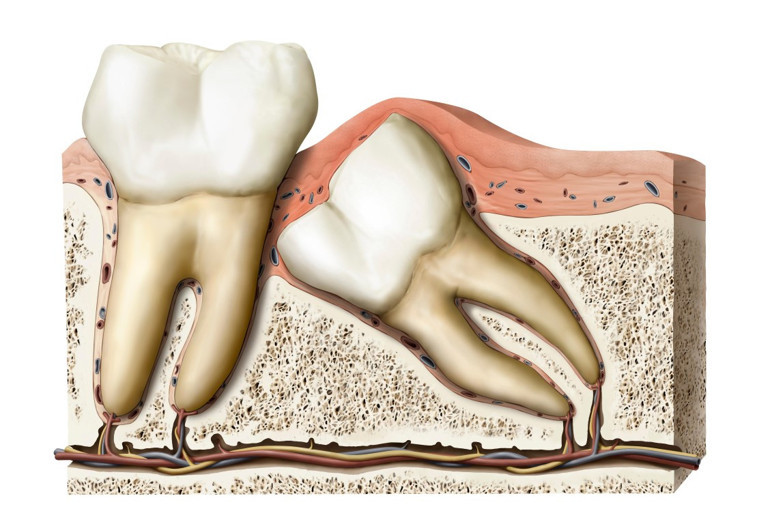

2) Yirmi yaş dişlerinin çekimi normal diş çekiminden neden daha zor? Neden ameliyatla çekilmek durumunda kalınıyor?

“Çene kemiğinde en arkada yer alan yirmi yaş dişleri çıkamadığı zaman adı üzerinde 'gömülü' kalıyor, bu durumda üstünde bir miktar kemik engeli de olunca, buradan serbestleştirerek alınması gereken yirmilik dişler çoğunlukla operasyon ile çekilebiliyor.”

Öztürk, yirmi yaş dişlerimizin, atalarımız bugünkü gibi işlenmiş gıdalarla beslenmediklerinden dolayı, çiğ et ve sebzeleri parçalayabilmek için kafatasımızda yer etmiş olan çiğneyici dişler olduğunu, günümüzdeki modern beslenme modelinde bu dişlerin normal bir çene fonksiyonu için gerekliliğinin kalmadığını belirtti. Bununla beraber Öztürk, küçülen kafatasında yer bulmakta zorlanan yirmi yaş dişlerinin gömülü kalabileceğini ya da çıkmak için yer bulamayınca enfeksiyon gibi sorunlara yol açabileceğini ve şiddetli ağrılara neden olabileceğini söyledi.

Love, alt çenedeki üçüncü azı dişin genellikle inferior alveolar adlı sinire yakın olduğunu, olası sinir hasarında yanma, iğne batması ve uyuşma hissinin ortaya çıkabileceğini, bunun genç yaşta geçici, ileri yaşlarda ise kalıcı olma ihtimalinin daha yüksek olduğunu belirtti.